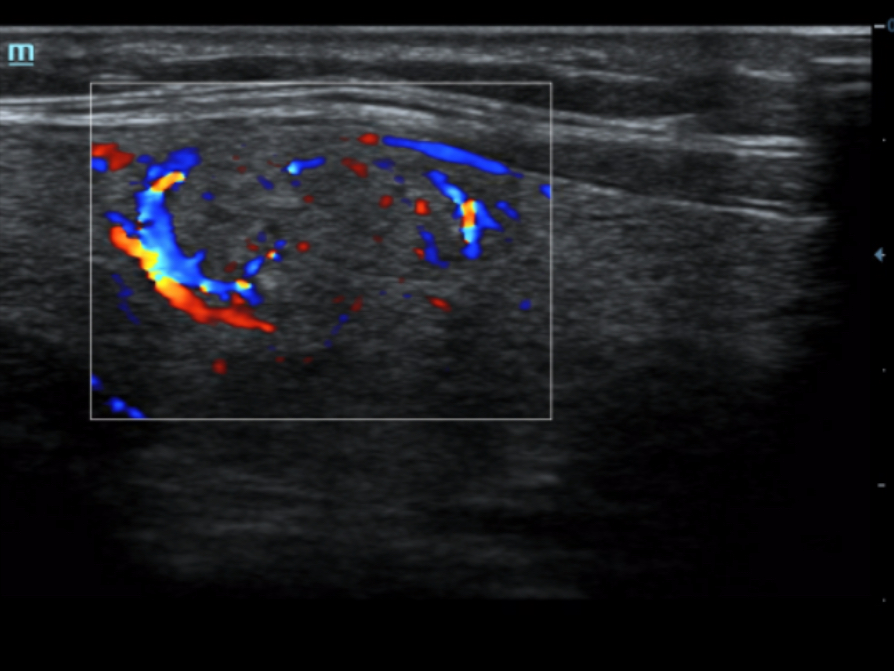

HR Flow?

Funci√≥n √Їnica de Mindray: Una funci√≥n √Їnica de Mindray: realice un seguimiento continuo del flujo de color y optimice la mejor posici√≥n del cuadro de color y el mejor √°ngulo en la adquisici√≥n de im√°genes en tiempo real.